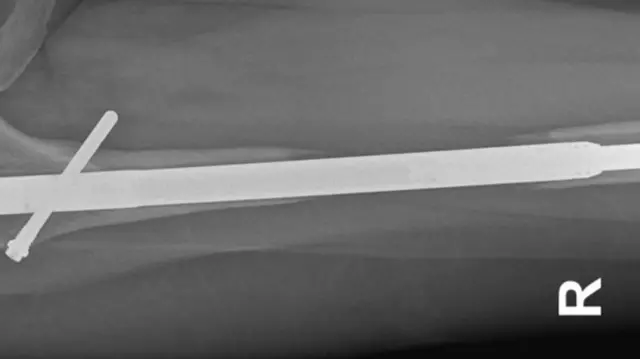

ఈ ప్రొసీజర్లో కొంత నొప్పి ఉంటుందని ఊహించాం. కానీ, ఆపరేషన్ సమయంలో కాళ్ల ఎముకలు రెండుగా చీల్చారు. లోహపు కడ్డీలు లోపల పెట్టారు.

ఈ లోహపు కడ్డీలు వాటి పొడవును పెంచుకునేందుకు క్రమంగా విస్తరిస్తాయి. ఈ సమయంలో ఎముక రెండు భాగాలు వేరువేరుగా అవుతాయి. ఈ ప్రక్రియ మెల్లగా రోగి ఎత్తును పెంచేందుకు ఉపయోగపడుతుంది. విరిగిన ఎముకలు తిరిగి క్రమంగా అతుక్కోవాలి. వాటి మధ్యలో ఉన్న గ్యాప్ను పూడ్చుకోవాలి. ఈ ఆపరేషన్ చాలా క్లిష్టమైంది.

మళ్లీ డాక్టర్ గీషెట్ను ఆశ్రయించారు ఎలైన్. మిలాన్లో తాను పనిచేసే క్లినిక్లో గీషెట్ మరో ఆపరేషన్ చేశారు. 2017 ఏప్రిల్లో ఎలైన ఎడమ కాలు పొడవు పెరగడం మొదలైంది. అలాగే ఎముకను పెంచేందుకు కుడి కాలిలోకి బోన్ మారోను ఇంజెక్ట్ చేశారు. ఆపరేషన్ తరువాత ఎలైన్కు మరింత భయంకరమైన వార్త తెలిసింది.

లోహపు కడ్డీ ముక్కను బయటికి తీస్తున్నప్పుడు అది విరిగిపోయిందని డాక్టర్ గీషెట్ చెప్పారని ఎలైన్ తెలిపారు.